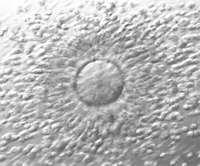

Després de la fecundació els embrions se segueixen al laboratori. Són supervisats pels biòlegs i monitoritzats per assegurar el seu correcte desenvolupament en les fases inicials. Es mantenen en incubadores, a temperatura constant, en medis de cultius adequats per a la seva correcta evolució.

Entre dos i tres dies després es procedeix a la seva avaluació i selecció per transferir-los a la pacient i/o vitrificar-los. No tots es desenvolupen correctament, alguns interrompen el seu desenvolupament i, aleshores, es descarten per a la transferència.

En alguns casos, per diferents motius, es considera indicat allargar el cultiu dels embrions fins a una fase més avançada del desenvolupament, denominat "blastocist" i es transfereix el 5è o 6+e dia de desenvolupament.